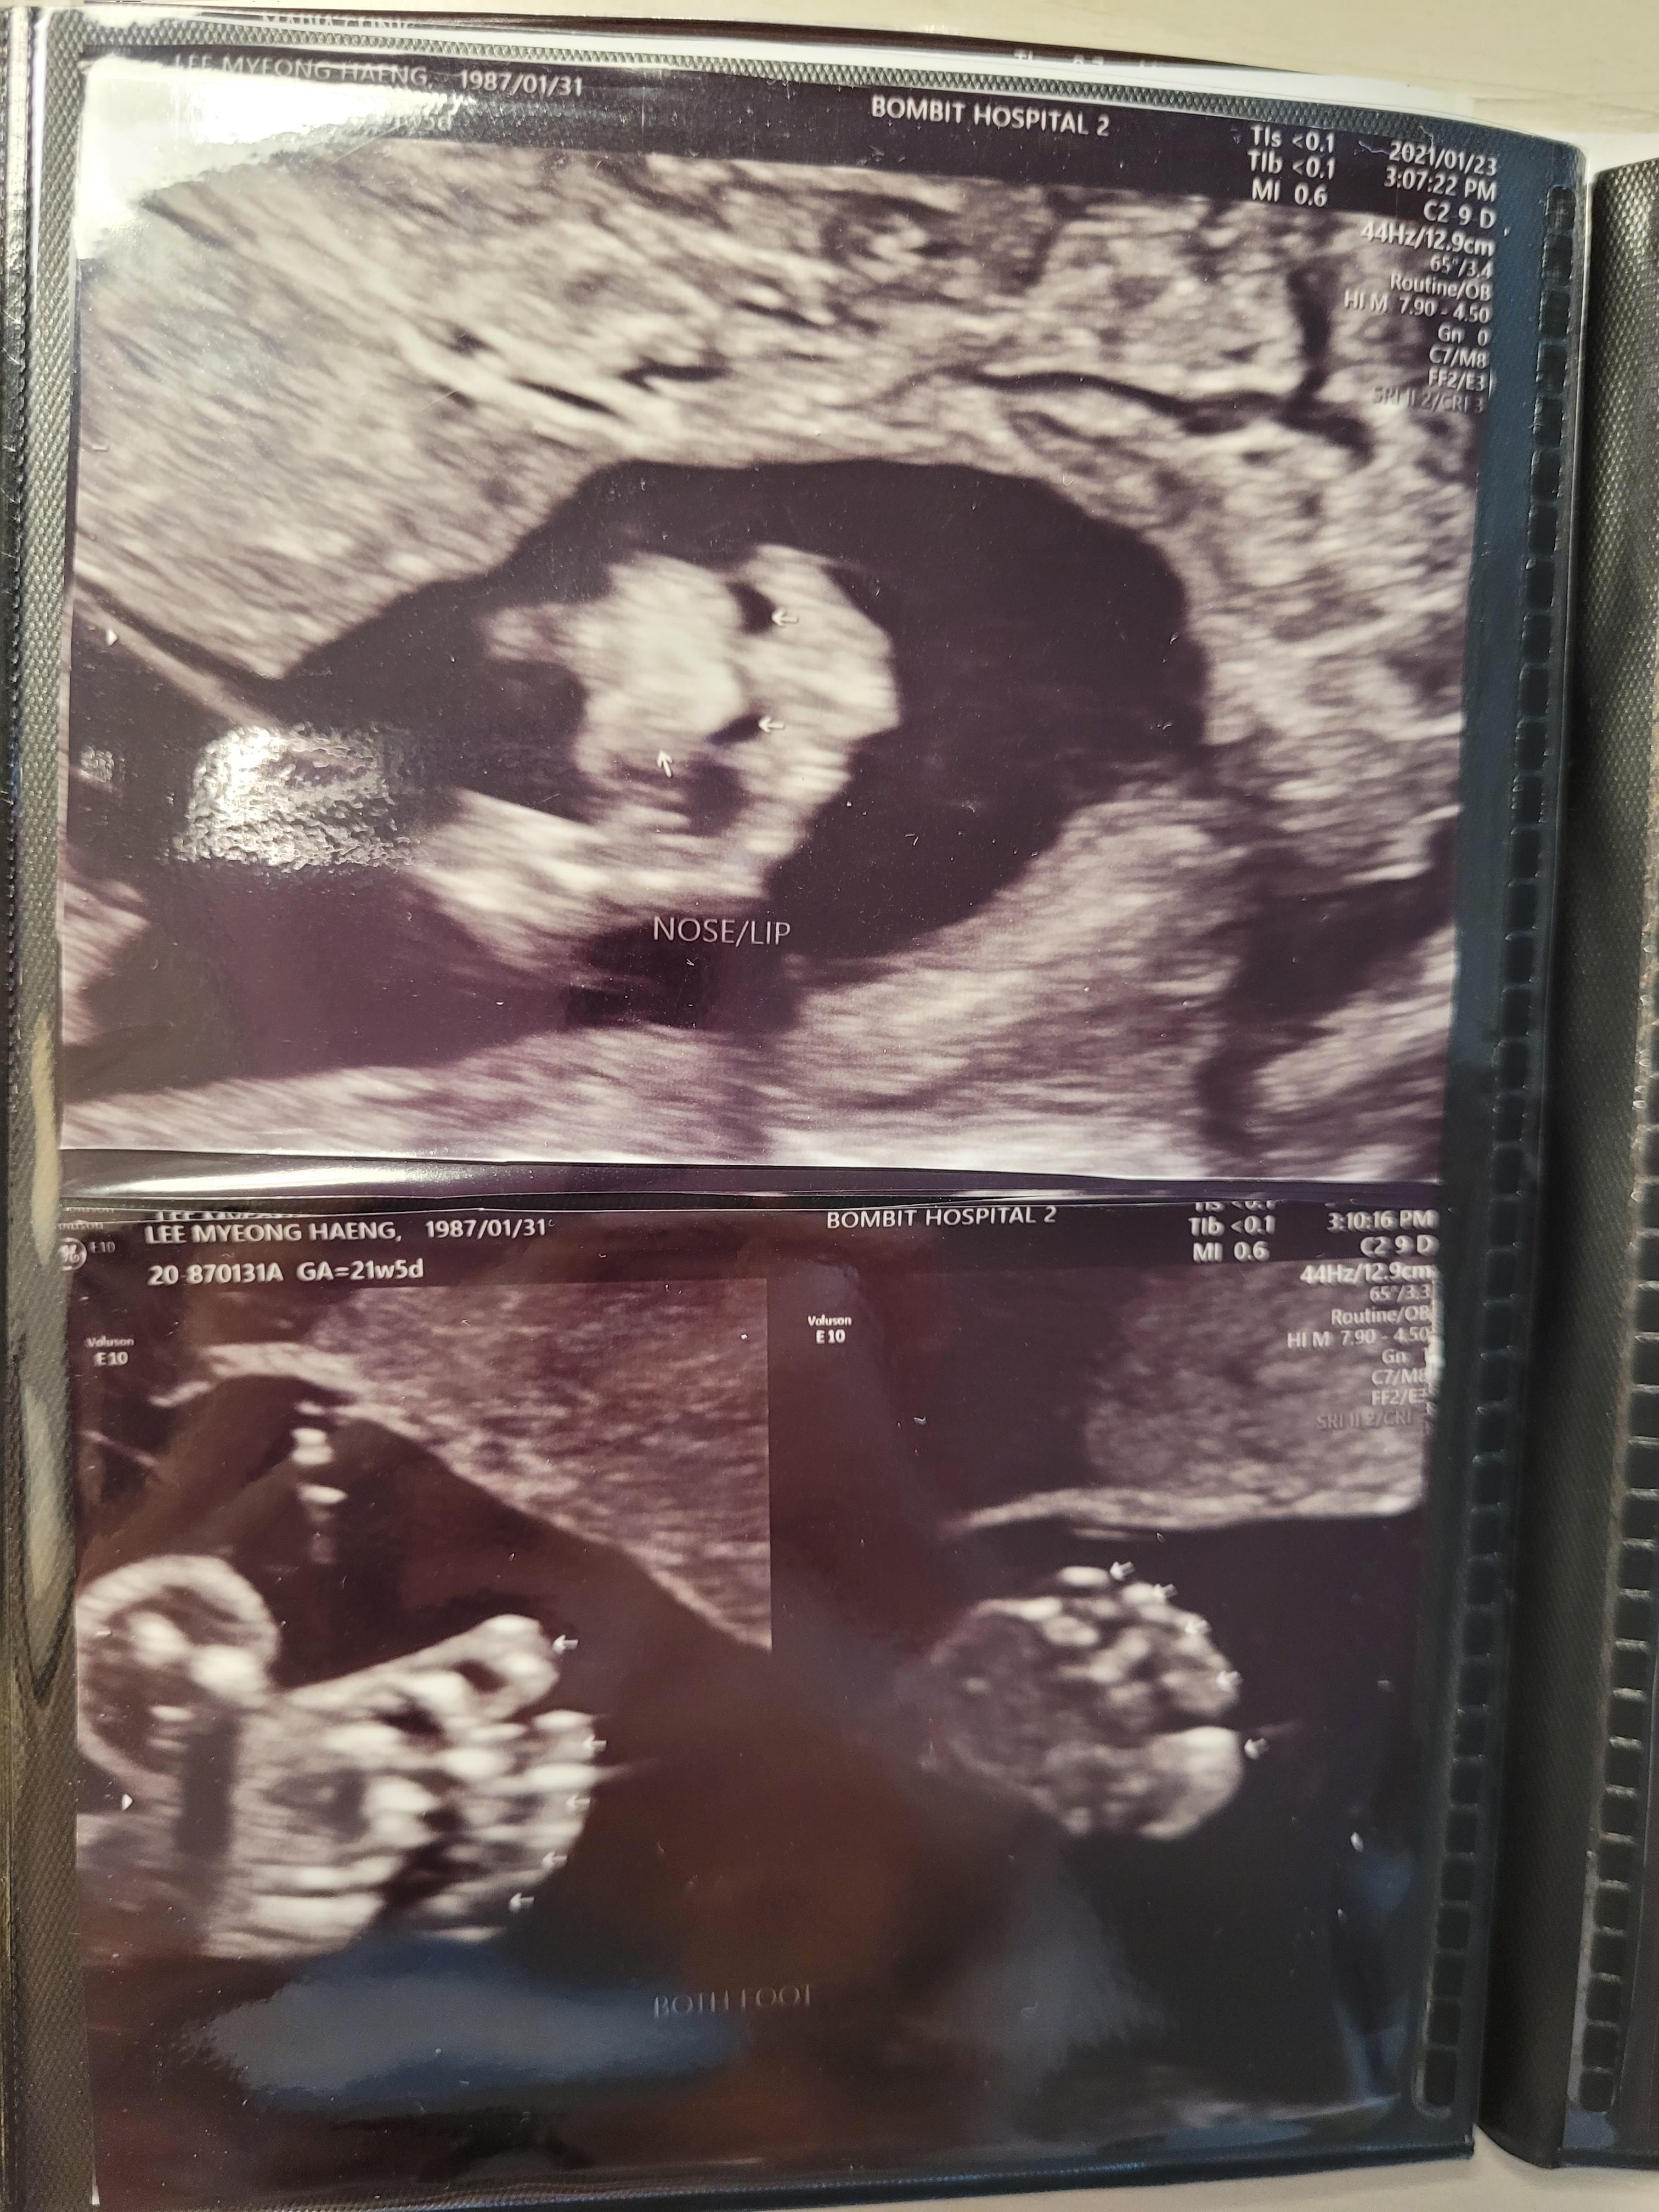

20주 6일 중기 정밀 초음파 초음파를 무려 27분 동안 봤다.(영상은 15분까지 잘리는 것 같아 TT) 머리 주위에서 시작해서 뇌조직, 척추심장, 상방광, 손가락, 발가락, 구순구개 유무, 허벅지 정강이가 귀 폐 배꼽 위에 혈류 소리까지 모두 너무 신기하고 재미있었다.

그래도 귀여워!! 코랑 입술이 너무 잘보여서 신기했다.양수도 적당하고 경부 길이도 3.935cm로 양호!그 다음에는 진료를 받으러 3층으로 갔다.왠지 피곤해 보이는 #김정은 원장, 그래도 여전히 친절했다.함께 초음파 결과를 빨리 보고 정상 확인했고 아직 체중이 줄어든 상태라 걱정의 말씀도 해주셨다.(이제 잘 먹으니까 괜찮아요!!를 외쳤어 ㅎㅎ) 오메가3를 모르고 먹지 않아서 깜짝 놀라 새로 구입하기로 했고 간혹 있는 복통이나 분비물이 문제가 없는지 궁금했는데 괜찮다고 했다. 그리고 이날 #B형간염 예방접종을 시작했다.

B형 간염 접종은 용량이 많아서 아프다더니 진짜 리얼… 아팠다.A형까지 이걸 4번이나 맞아야 하다니.이날 진료비는 67,900원 초음파(본인부담) 42,615원+B형간염(비급여) 23,000원+진찰료! 바우처는 벌써 절반 이상 썼다. 잔액 47만원의 다음 진료는 닌텐도 검사로 단식은 없지만 너무 단 것을 먹고 오지 말라고 했다.숙숙이는 건강하게 자라고 있었고, 항상 새롭고 귀엽고, 다음에도 건강하게 만나자.#임신20주6일 숙숙이는!! 몸무게380g 머리직경(BPD)4.71cm 허벅지(FL)3.42cm 머리가 작고 허벅지가 길다

옆모습! 혀까지 잘 보여

발가락 열 개

왼손으로 얼굴을 반이나 가리다.